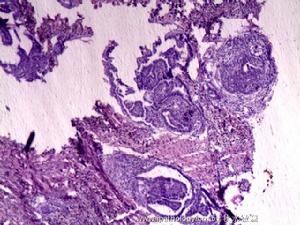

甲狀舌囊腫內多覆有復層柱狀上皮、復層扁平上皮或移行上皮。囊液為粘液性,感染後為膿性。上皮下可見有甲狀腺組織。